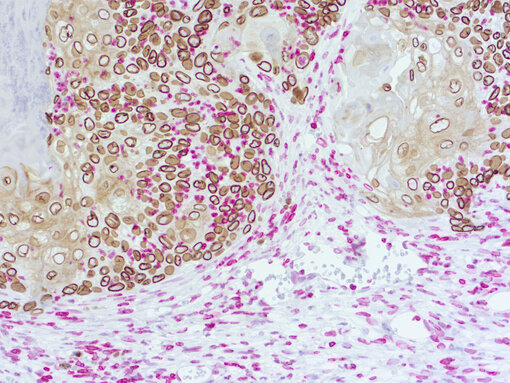

Immunohistochemical doublestaining of patient-derived lung cancer model

Figure 3a: Immunohistochemical doublestaining of patient-derived lung cancer model using rat anti-human Lamin B1 (cat.no. HS-404 017; DAB, brown color) and rabbit anti-mouse Lamin B1 (cat.no. HS-404 003; AP-RED, red color). Nuclei were counterstained with haematoxylin.

Figure 3b: Immunohistochemical doublestaining of patient-derived pancreas cancer model using rabbit anti-human Ki67 (cat.no. HS-398 003; AP-RED, red color) and rat anti-mouse Ki67 (cat.no. HS-398 117; DAB, brown color). Nuclei were counterstained with haematoxylin.